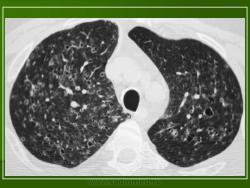

В 5 наблюдениях (21%) из больных с распространенной формой заболевания отмечались изменения в легких в виде обогащения, избыточности легочного рисунка, его деформации по сетчато-петлистому типу, очаговых теней. Корневая и медиастинальная аденопатия отсутствовали. В 1 случае в легких выявлена киста, которая периодически осложнялась нагноением (Рис. 4).

Поражение легочной ткани (рис. 22) свойственно любому возрасту. Часто больные имеют общие симптомы — лихорадку, слабость, реже — кашель, одышку, боли в грудной клетке. На рентгенограммах отмечается деформация и усиление легочного рисунка и микроузловые инфильтративные тени. Поражение костного мозга (с наличием клеток Лангерганса) сопровождается цитопенией периферической крови.

Рис. 22. Поражение легких при Лангер-гансово-клеточном гистиоцитозе.